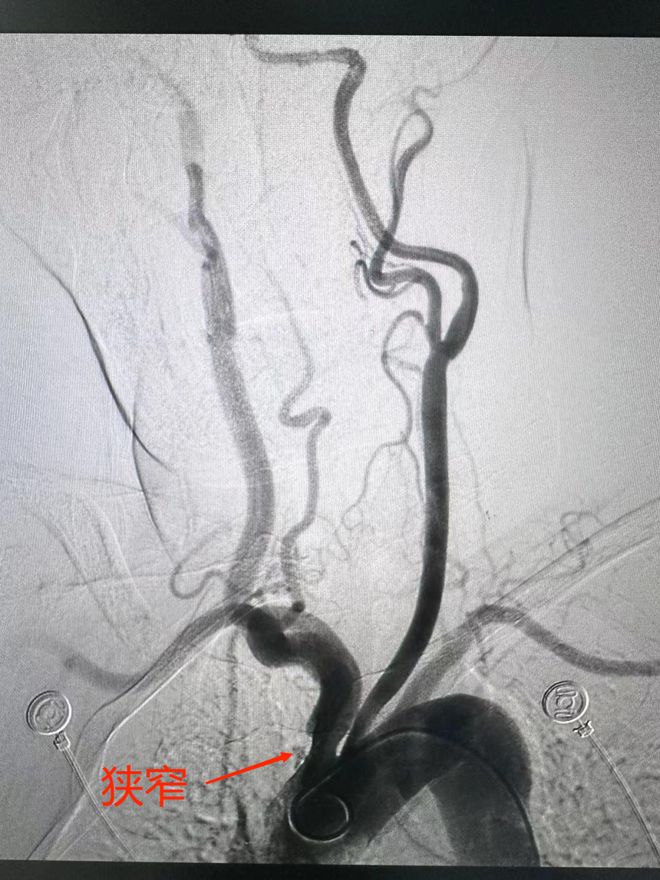

什么是磁共振血管造影

磁共振血管造影是一种利用核磁的流空效应来显示血管的新技术,其操作过程主要包括以下步骤采集图像资料首先,通过磁共振设备采集一系列连续薄层的断面图像资料这些图像资料是后续进行血管重建的基础图像后处理采集完图像资料后,需要...